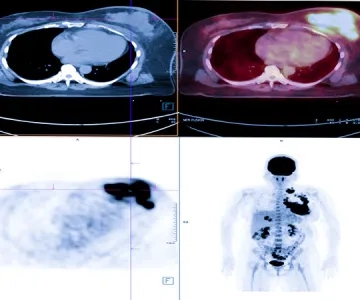

Nuclear Medicine methods are increasingly used in the treatment of cancer, as well as imaging. Targeted atomic therapies have been developing at a stunning pace since 2010.

Theragnostic is a field of medicine that combines patient-specific and disease-targeted diagnosis with treatment. The most important feature of atomic treatments with radionuclides is that the diagnosis can be made with the same drugs, and this provides an extraordinary advantage in cancer treatment. This feature ensures that the drug given for treatment, the area where it will reach in the body, and its effect on the diseased tissue are known precisely before the treatment. This approach is called the “theragnostic” approach.

Unlike conventional chemotherapeutics, theragnostic drugs go directly to the cancer cell, with little or no effect on normal cells. Thus, while healthy cells suffer the least damage, targeted therapy is performed by giving maximum damage to diseased cells such as cancer cells.